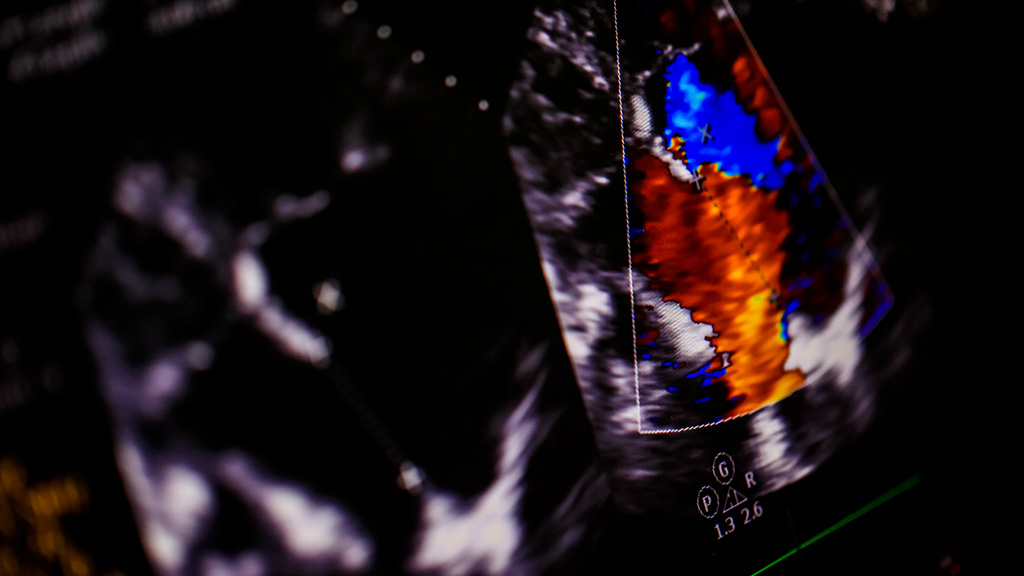

Ultrasonido Doppler Color Higado